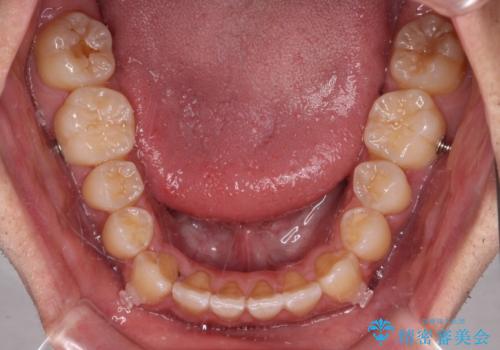

- 前歯のデコボコを気にして来院された患者様です。

歯列としてはワイヤー装置でもインビザラインでも対応可能でしたが、インビザラインが苦手とする上顎側切歯(真ん中から2番目の歯)の舌側転位が顕著でした。

治療の確実性を上げるために、インビザライン開始前に上顎のワイヤー装置にて舌側転位を解消し、その後インビザラインにて矯正治療を行うこととしました。

前歯のデコボコが早めに改善され、スムーズに治療を終えることができました。